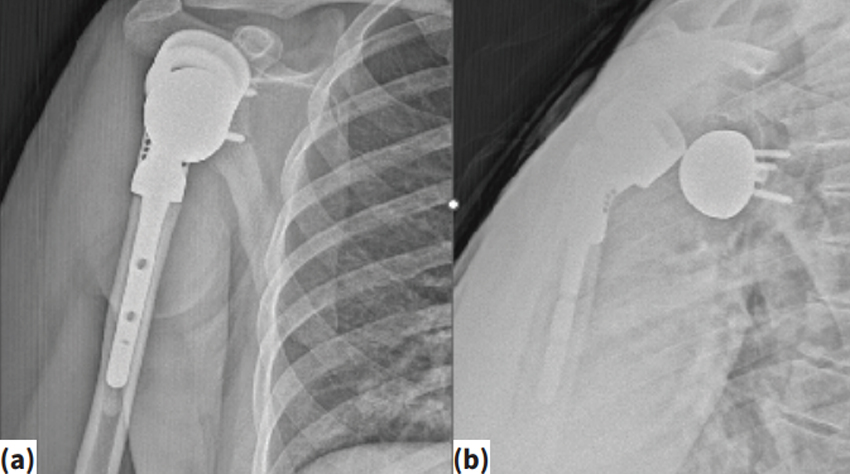

Devamı...Omuz çevresi tümörlerde ters omuz proteziReverse shoulder prosthesis for tumors around the shoulderVolkan Gürkan1 , Muzaffer Ağır2 , Fatih Yıldız3 1 Avicenna Umut Hastanesi, Ortopedi ve Travmatoloji Kliniği, İstanbul 2 Acıbadem Üniv...

Devamı...Harzem Özger1 · Bugra Alpan2 · Ahmet Salduz6 · Volkan Gurkan3 · Mustafa Sungur4 · Natig Valiyev5 · Levent Eralp1Bezmiâlem Vakıf University Faculty of Medicine, Department...